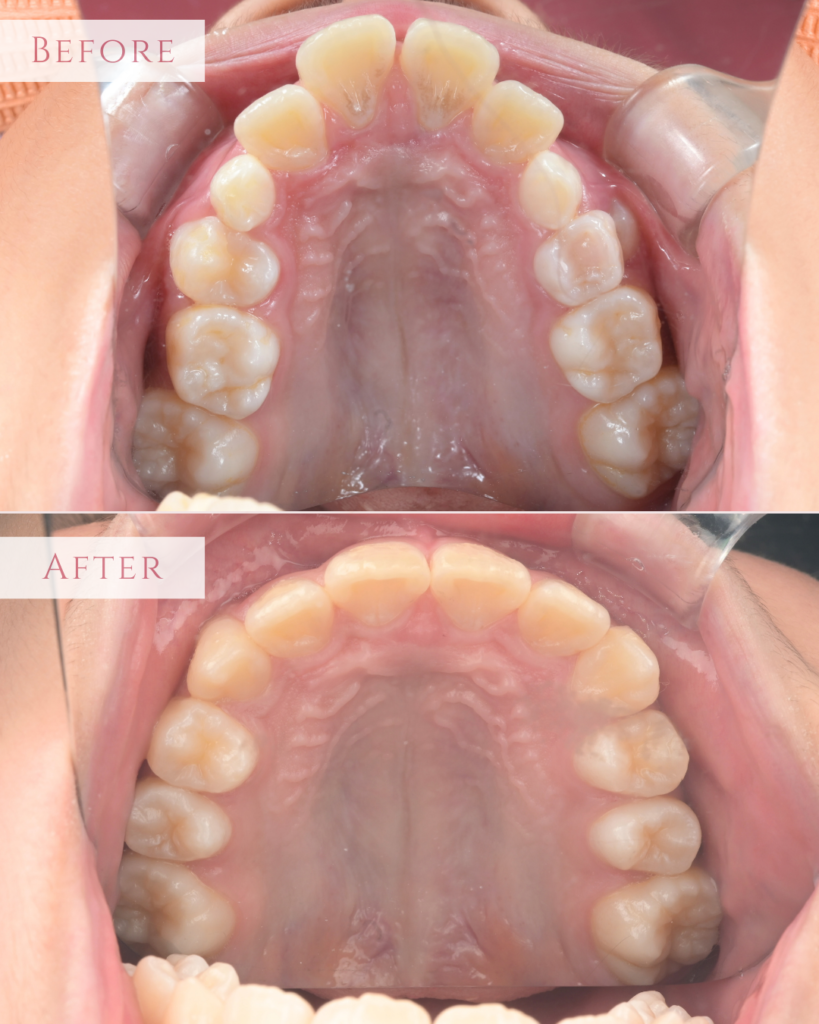

【4】上顎の咬合面

治療前は、歯列のアーチが狭くV字型をしており、これから生えてくる永久歯のためのスペースが不足していました。 治療後は、左右にきれいに拡大され、理想的なU字型のアーチになりました。永久歯が並ぶための土台が整いました。